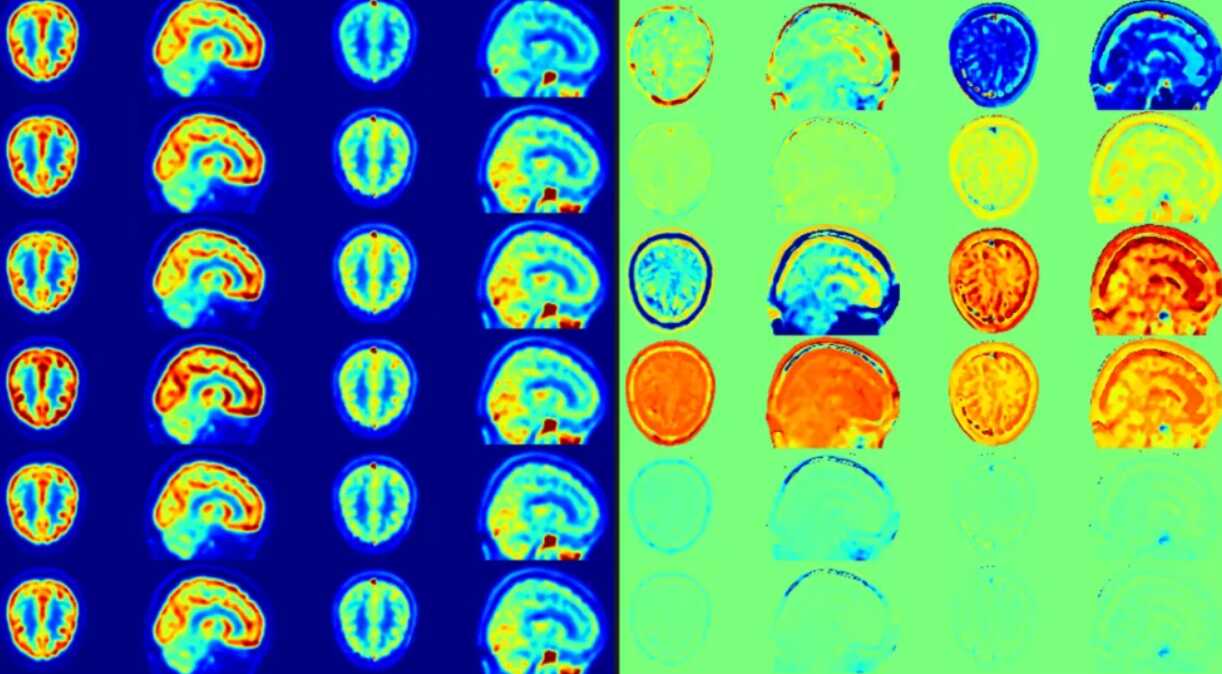

IEEE TMI | 基于深度学习无创获得血液输入函数,助力动态脑PET定量成像

全面量化大脑PET图像,常常需要精确的血流输入函数。然而传统方法中,获取这一函数通常依赖于侵入性且耗时的动脉导管采血,这在临床实践中往往难以实现。

全面量化大脑PET图像,常常需要精确的血流输入函数。然而传统方法中,获取这一函数通常依赖于侵入性且耗时的动脉导管采血,这在临床实践中往往难以实现。7月2日,中国科学院深圳先进技术研究院(以下简称“深圳先进院”)孙涛副研究员课题组与河南省人民医院王梅云副院长团队合作,在医学...